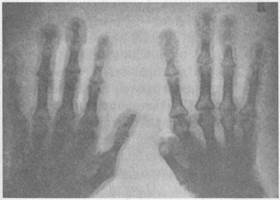

Объективно. При осмотре в начальной стадии болезни су­щественных изменений не выявляется. При развитии дыха­тельной недостаточности появляется диффузный (централь­ный) серый или «чугунный» цианоз кожи, обусловленный ар­териальной гипоксемией. Цианоз усиливается при компенса­торном эритроцитозе. В отличие от сердечного акроцианоза при легочном диффузном цианозе кожа на ощупь теплая. У больных с декомпенсированным хроническим легочным серд­цем наблюдается более интенсивное синюшное окрашивание

губ, ушных раковин, кончиков пальцев рук (акроцианоз) за счет сердечной недостаточ­ности. При хроническом гнойном бронхите часто обнаруживаются симптомы «барабанных палочек» и ногти в виде «часовых стекол».

Грудная клетка эмфизе­матозной формы («бочкооб­разная»), малоподвижная при дыхании (рис. 42, 43). Шея короткая из-за высокого стояния верхушек легких, при